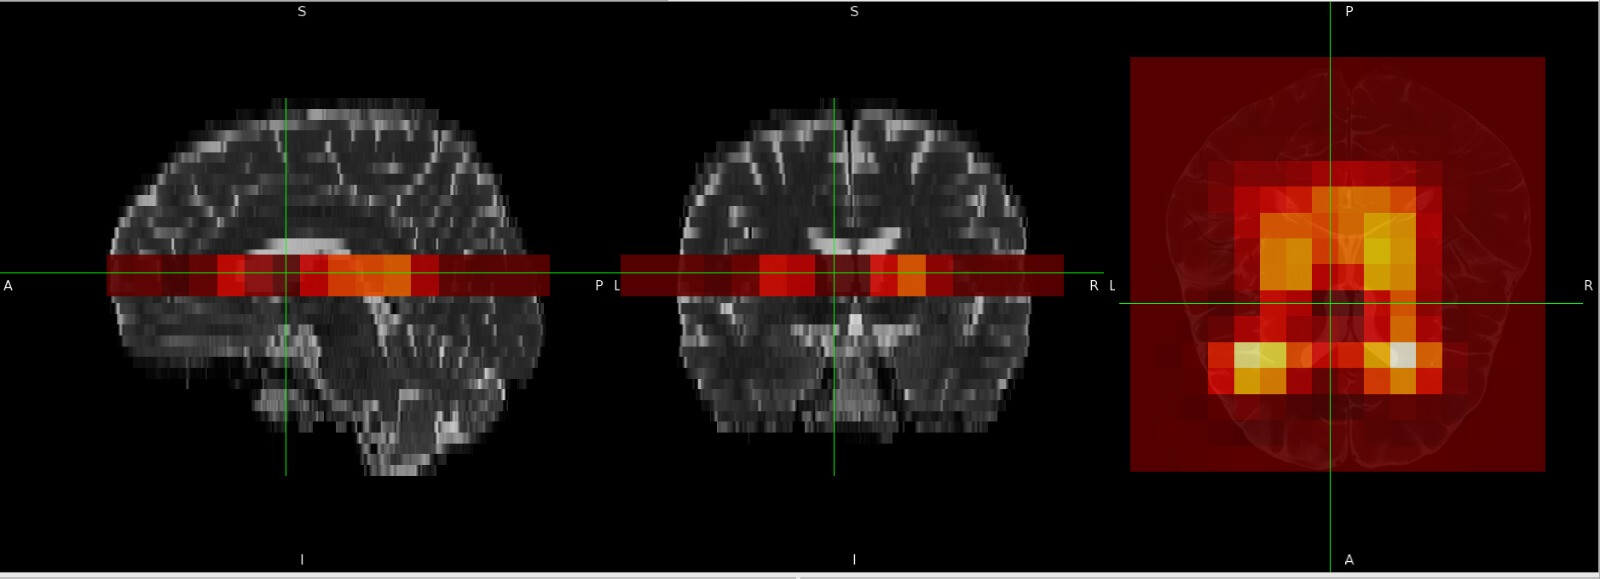

Actually @ardacanbas1 I think spec2nii might be doing the right thing anyway. The reason it appears with no orientation, is that you are viewing the data in the frame of the structural image, which has a rotation and to which the MRSI is somewhat matched to.

This is the data viewed in the World coordinates Display space (which is aligned with the scanner’s gradient frame)

where an orientation is obvious. When we switch to the structural image sub1_Bet space with the same data, we see most of the orientation disappear in both:

The latter is what gets selected automatically when fsleyes is loaded (otherwise you see the tearing apparent in the first view). You can change it by finding the Display Space option in the ortho view View Settings menu look for the

Note there looks to be an AP/LR shift in the data but I think that’s because of the CSDE of the water residual, which is the dominant signal